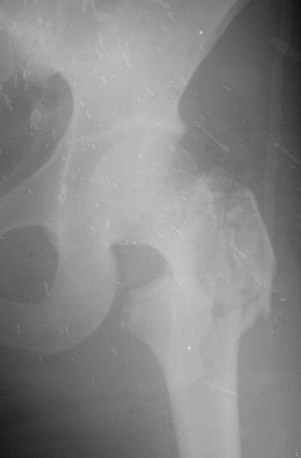

Перелом бедра

Уважаемые коллеги! На консультации обратились родственники больной, получившей в автопроисшествии неделю назад вот такой закрытый перелом.

Что делать? Пациентке 25 лет.